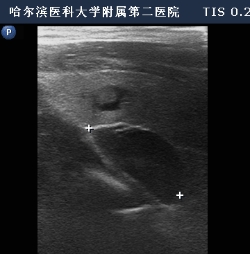

高频超声检查显示刘先生右侧甲状旁腺腺瘤

在局麻下,姜双全为刘先生进行了超声引导下微波消融治疗,用时不到二十分钟,就顺利将甲状旁腺腺瘤完全灭活,仅留下不到2毫米的针眼,术后15分钟采集静脉血结果显示甲状旁腺激素值从2000 pg/ml直接下降到150 pg/ml,第二天激素水平及钙离子均恢复到正常范围,刘先生转危为安,身体不适症状消失。同日,在顺利脱离连续血液净化治疗后,转回普通病房。